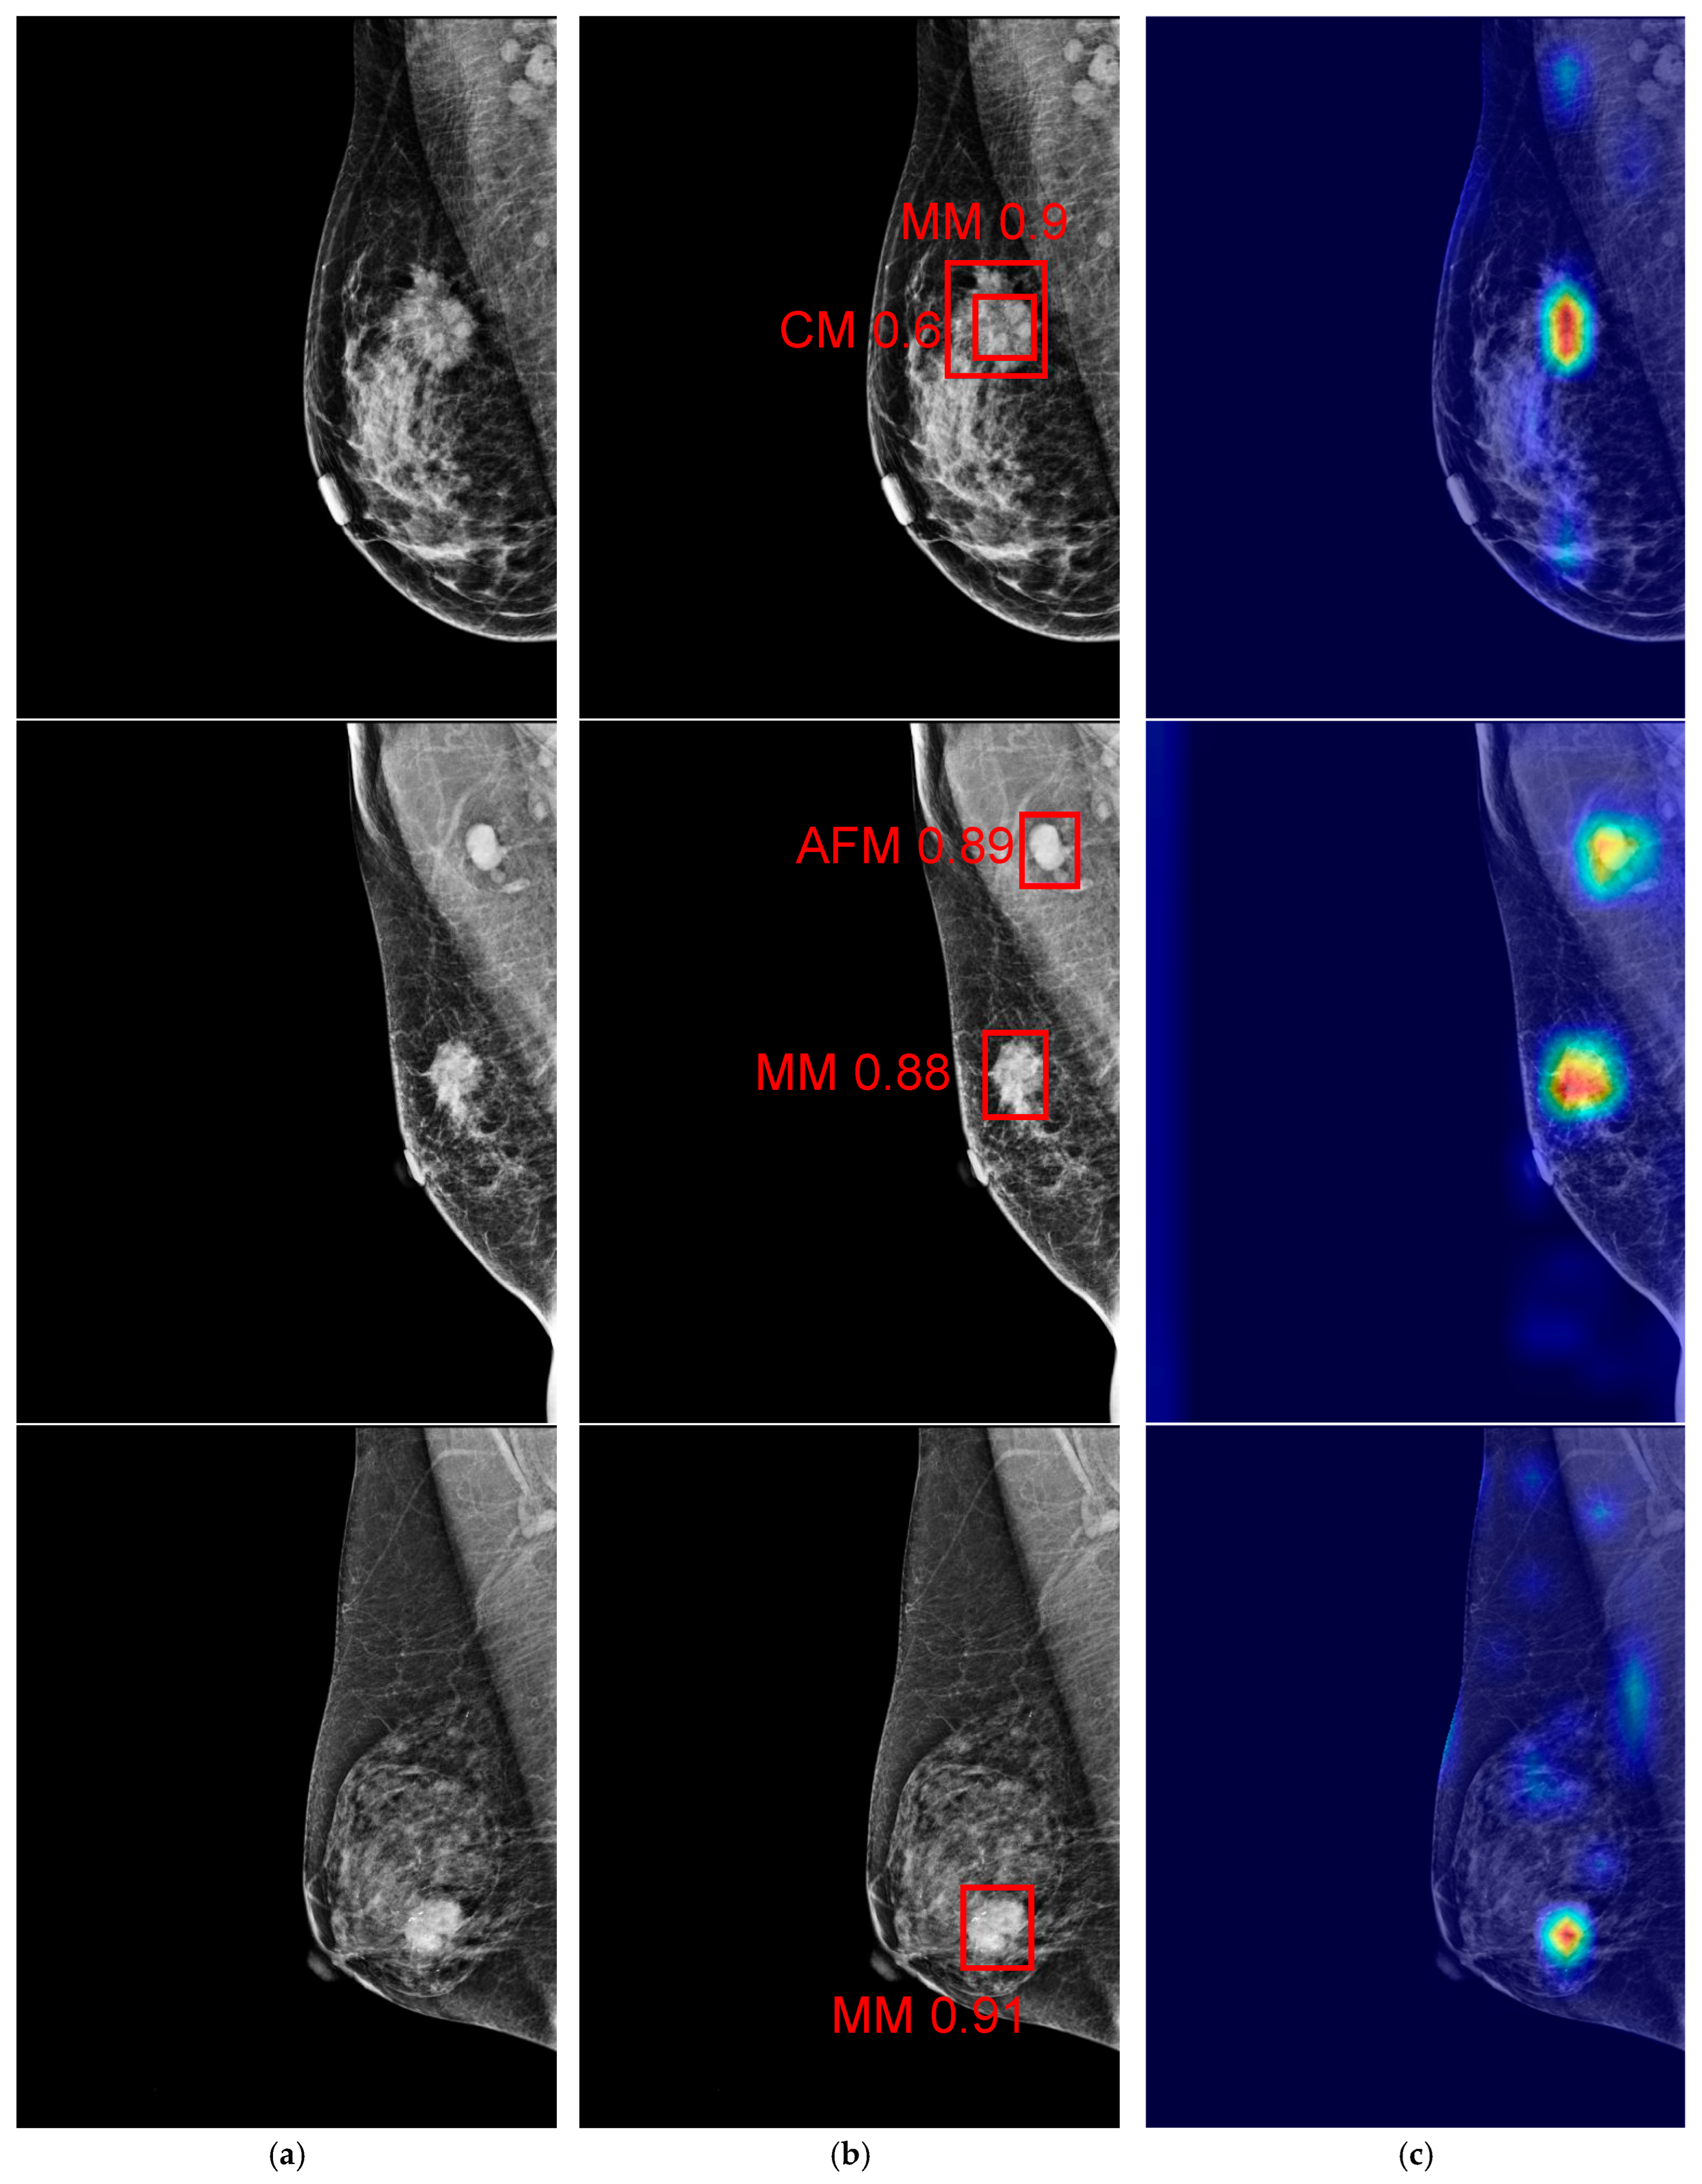

4. Results and Discussion

4.3. Experiment 3: Deploying a Mammogram on the NVIDIA Jetson Nano Board